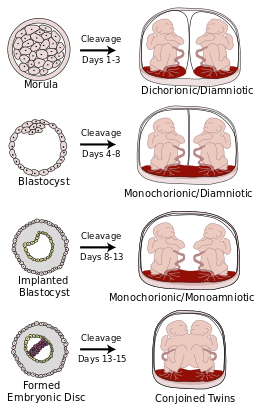

Fraternal twins are dizygotic. This means that two eggs are each fertilized by two different sperm. This results dichorionic-diamniotic twins where the two embryos each have their own placenta and amniotic sac. Fraternal twins are the most common and lowest risk type of twins. Read more about di-di twins here.

Identical twins are monozygotic. This means they that one egg (mono = one) is fertilized by one sperm. The egg then splits between 3 and 12 days after fertilization, resulting in two embryos that share one placenta and are therefore monochorionic.

The two most common types of identical twins are:

- Monochorionic Diamniotic (Mo-Di or Mono Di) twins share the same placenta and each baby has its own amniotic sac.

- Monochorionic Monoamniotic (Mo-Mo or Mono-Mono) twins share both the placenta and amniotic sac.

Sometimes in a monozygotic (identical twin) pregnancy, the egg splits very early and develops two placentas. Known as di-di identical twins, they can appear to be fraternal on ultrasounds. Occurring in up to 30% of identical twin pregnancies, only a DNA zygosity test after birth can confirm that they are identical.